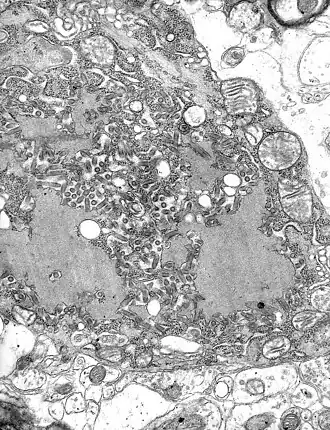

Descrição

A - Corpúsculos de Negri livres;

B - Corpúsculos de Negri em célula nervosa

O virião tem em geral a forma de um projétil (arredondada numa extremidade e reta na outra), podendo também ter formato de bacilo (as duas pontas arredondadas), medindo cerca de 170 nm de comprimento por 70 nm de largura.[3]

O revestimento lipídico (4, na imagem) é cercado por uma camada de espículos de glicoproteína, com cerca de 5 a 10 nm de comprimento[1] (2, na imagem). O nucleocapsídeo tem formato helicoidal simétrico (3) e é envolvido por uma camada lipídica (5).[1]